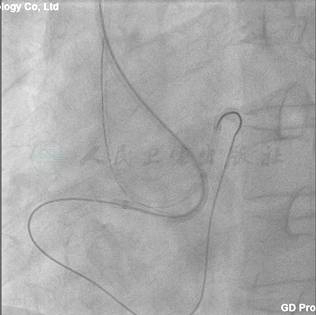

由于RCA有明显清晰的残段,成功率比较高。故应用6F JR 4指引导管,选用Pilot 150导丝,但是导丝却轻易进入假腔(自身侧支循环证实)(图6)。

图6 RCA行PCI,导丝却进入假腔